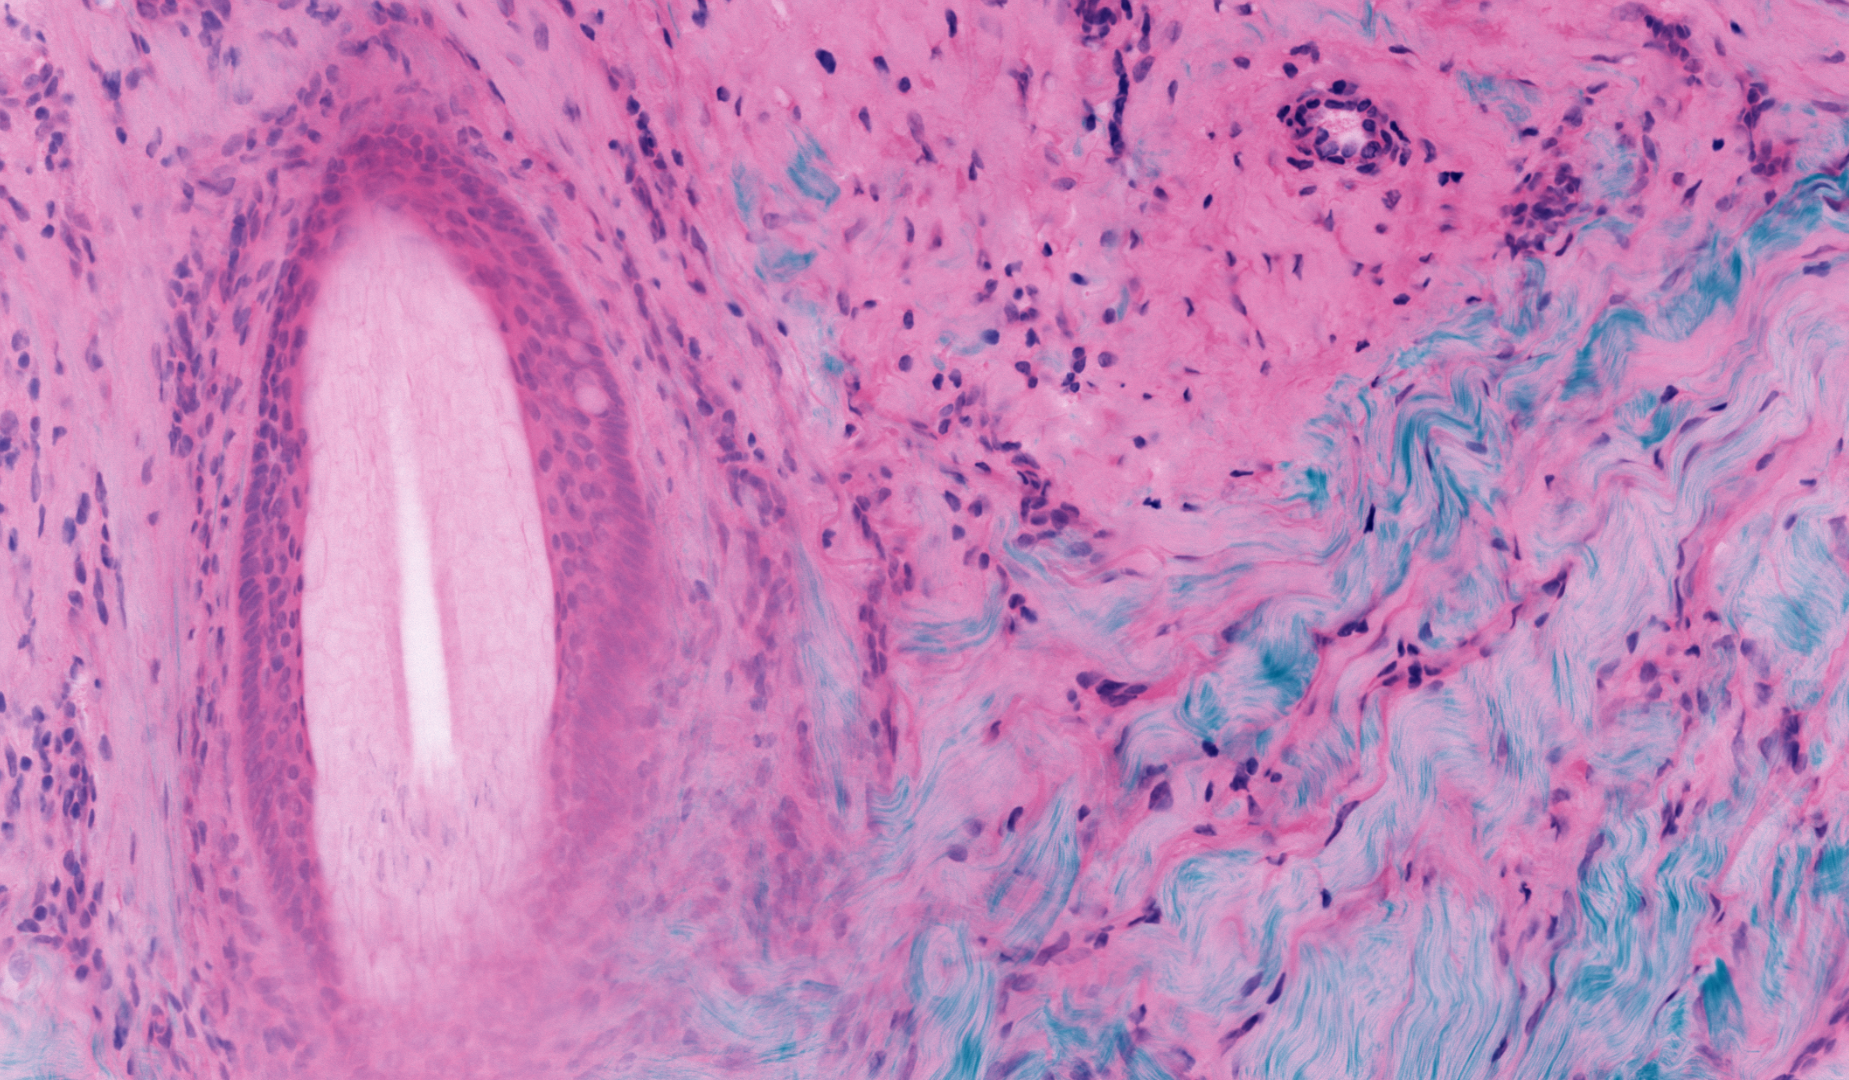

Magnification: Green is a fluorescent protein stain, red is a DNA stain, and blue is SHG in ordered Collagen tissue. DNA clusters in cell nuclei, proteins cluster in cell bodies, and collagen fibers form connective tissue in the skin sample. Image: Prof. Michael Giacomelli / University of Rochester